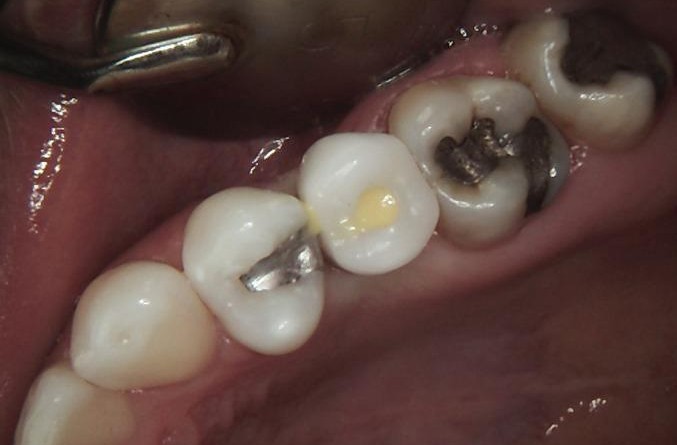

HEALING STAGE

During the healing phase, soft tissue maturation and integration were closely monitored. Soft tissues were carefully managed, using the Free Gingival Graft technique, which allowed for enhancing keratinised tissue and improving peri-implant tissue stability.

A healing cap was placed to guide soft-tissue contouring and support optimal formation of the emergence profile.